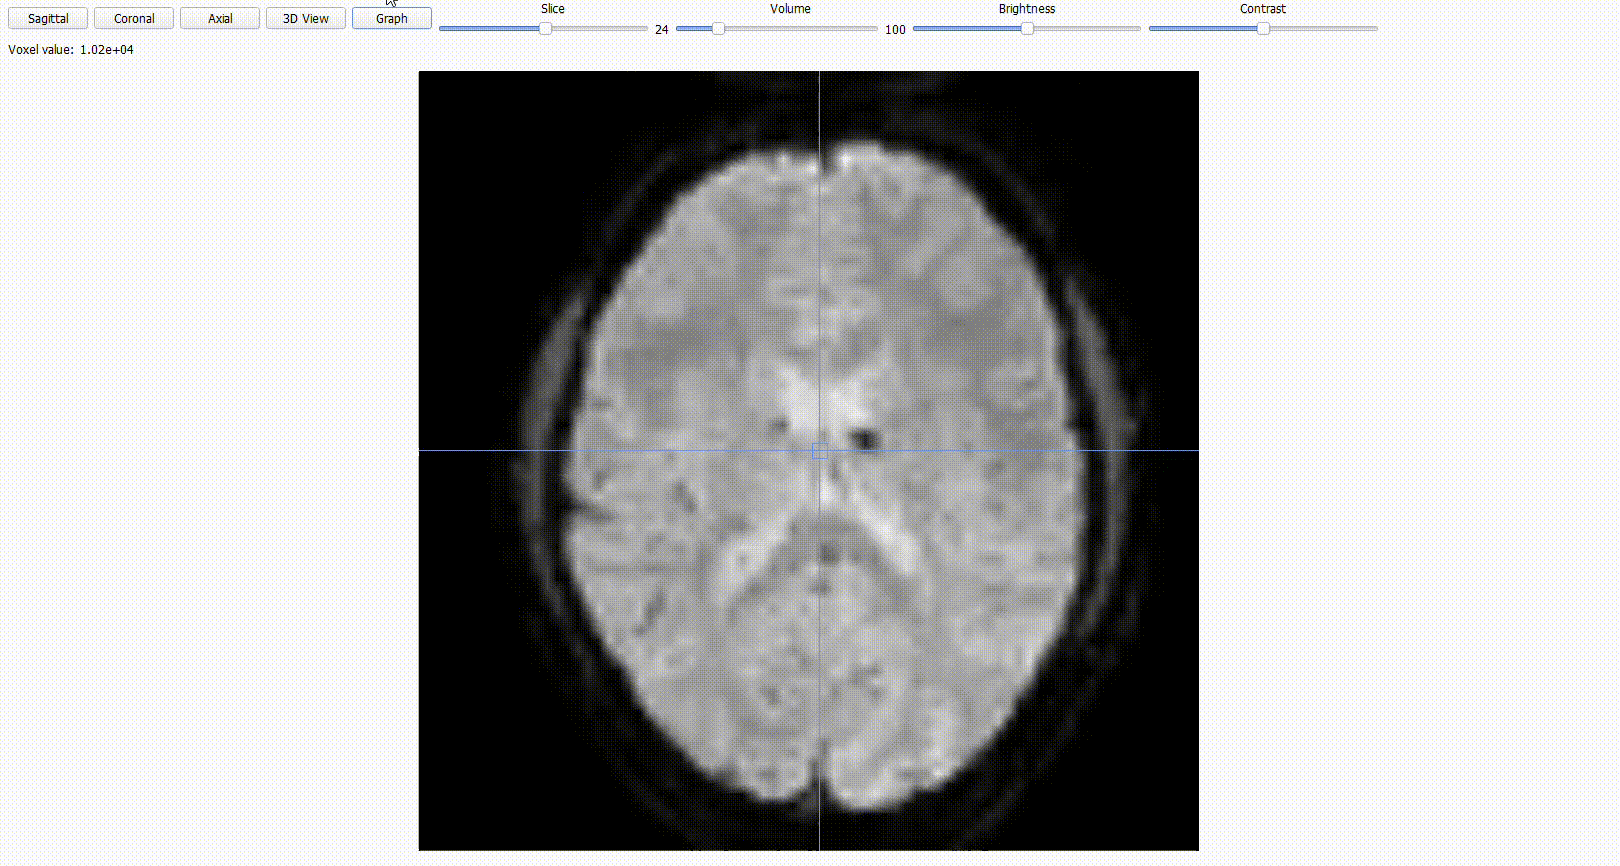

For functional (BOLD) images, you can scroll through time using the

volumetoggle.

BIDSplorer includes a

Graphoption for functional images that allows to see the how the signal changes over time. The graph along with thevolumetoggle will help you spot “jumps” or big irregularities that could be cause by the participant movements or scanner artifacts.

Expand the graph with the

Scopeoption (at the bottom of the screen) to include neighboring voxels, which can make artifacts easier to localize. You can also adjust theDot sizeor hide the neighboring dots.